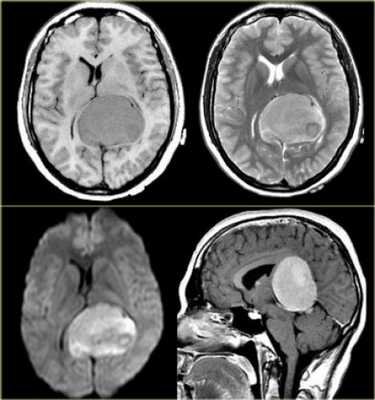

Опухоль пинеальной области головного мозга

К опухоли пинеальной области головного мозга относятся как к поражению железы шишковидной. Но нередко поражение возникает в средней части четверохолмия и задних отделах третьего желудочка. Здесь очень часто могут возникать такие поражения как карционома, гнерминома. Следует отметить, что пинеальные опухоли могут сочетаться с блоком ликовроциркуляции, что становится основой развития гидроцефалии.

Опухоли пинеальной области

Пинеальная зона — это сложная анатомическая часть, к которой относятся шишковидная железа, прилежащие мозговые структуры, ликворные пространства и сосуды.

Шишковидная железа располагается кзади от III желудочка мозга, кпереди и снизу от находится задняя спайка мозга, кпереди и сверху — comissura habenularum, ниже — четверохзолмная пластинка и водопровод мозга, а чуть выше и кзади — валик мозолистого тела.

Сразу за железой располагается четверохолмная цистерна. Распространяясь кпереди, эта цистерна образует velum interpositum, который лежит над шишковидной железой и идет кпереди под свод. Внутренние вены мозга и большая вена мозга находятся в непосредственной близости от пинеальной железы.

Клиника при образованиях шишковидной железы

- Внутричерепная гипертензия (компрессия водопровода, как следствие гидроцефалия).

- Синдром Parinaud (поражение среднего мозга).

- Мозжечковые расстройства.

- Эндокринная патология.

Эпидемиология

У взрослых опухоли пинеальной области составляют 0,5-1%, а у детей 3-8% от всех интракраниальных новообразований.